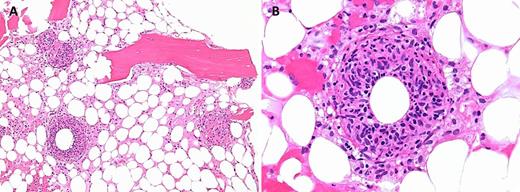

A 54-year-old man with a history of multiple myeloma presented with intermittent fevers, chills, fatigue, and weight loss for 1 month. A complete blood count showed leukopenia (white blood count: 1.4 × 109/L), mild anemia (hemoglobin: 12.4 g/dL), and thrombocytopenia (platelets: 100 × 109/L). Further testing revealed mildly elevated liver enzymes and splenomegaly. Of note, he had recently traveled throughout the southwestern United States, including Texas, for dove hunting on cattle ranches. The bone marrow biopsy revealed hypocellular marrow with panhypoplasia and multiple “doughnut” granulomas consisting of a central lipid vacuole surrounded by epithelioid histiocytes and a dense eosinophilic fibrin ring (panels A-B). Gomori-methenamine-silver and acid-fast-bacillus stains were negative on the biopsy. Serologic testing for fungal, HIV, cytomegalovirus (CMV), Treponema, and Brucella infections was negative. However, Coxiella burnetii serology testing by immunofluorescence assay showed phase 1 and 2 IgM titers >1:1024.

Q fever is an infection caused by the gram-negative intracellular bacterium C burnetii, which commonly results from the inhalation of aerosols that originate in infected birth products of domestic livestock and pets. Doughnut granulomas are highly evocative of Coxiella infections; however, they are not specific to Coxiella infections and have been seen in CMV, Epstein-Barr virus, Brucella and Salmonella infections, leishmaniasis, Hodgkin and non-Hodgkin lymphomas, and immune disorders.